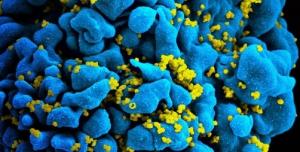

Actualité publiée il y a 10 années 3 moisPrEP vs VIH: La meilleure prévention pour les HSH à risque élevé

Actualité publiée il y a 10 années 3 mois